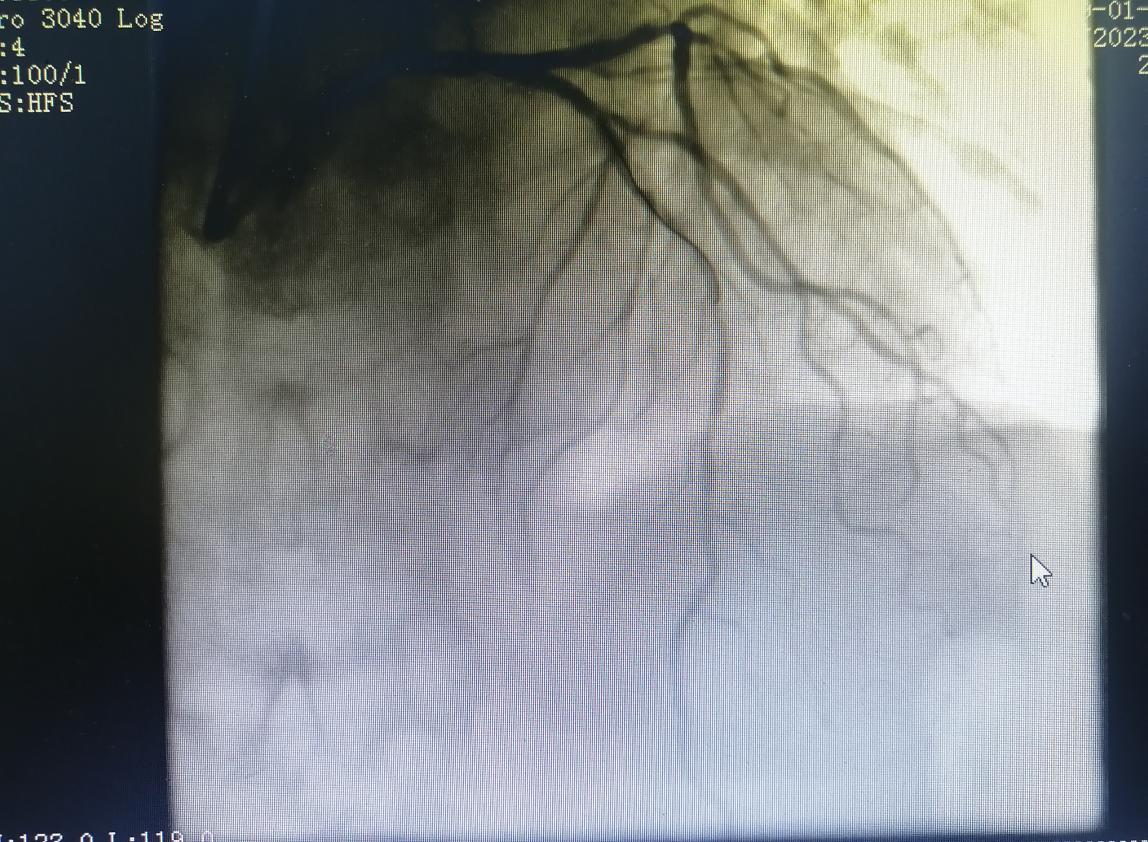

術(shù)前:

術(shù)后: